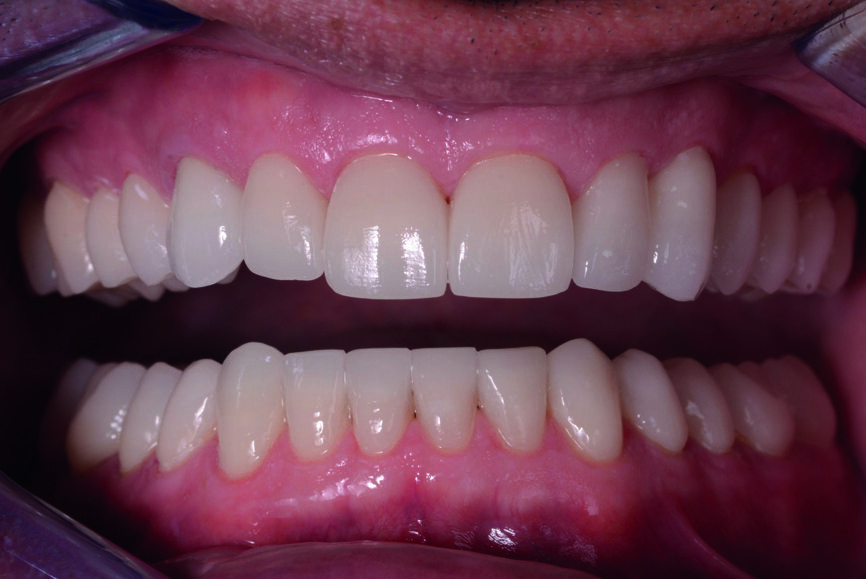

Figs. 16 et 17 : Photos de suivi en janvier 2021 montrant un résultat très stable sans aucun écaillage de la céramique et des avantages mécaniques constants mentionnés par le patient, tels que plus de céphalées de tension

Après l’élimination de l’excès de colle composite, l’occlusion est adaptée et vérifiée à l’aide du système d’évaluation occlusale T-Scan (Tekscan). Une contention amovible en résine acrylique est utilisée pour protéger les restaurations définitives, et celles-ci sont vérifiées six mois plus tard. À ce moment, les restaurations sont toujours stables et ne présentent aucun signe de fracture (Figs. 13–15). Le patient déclare également qu’il n’a plu souffert de maux de tête grâce à cette nouvelle dimension verticale d’occlusion.

Les développements des technologies dentaires permettent la mise en œuvre d’un traitement entièrement numérisé qui peut résoudre efficacement des problèmes tels que la perte de dimension verticale d’occlusion. Toutefois, par rapport aux techniques classiques, des études cliniques supplémentaires sont nécessaires pour parvenir à des résultats fiables du flux de travail numérique dans le cas d’une perte de DVO. Il est également indispensable de vérifier la fonction des restaurations définitives sur le long terme.